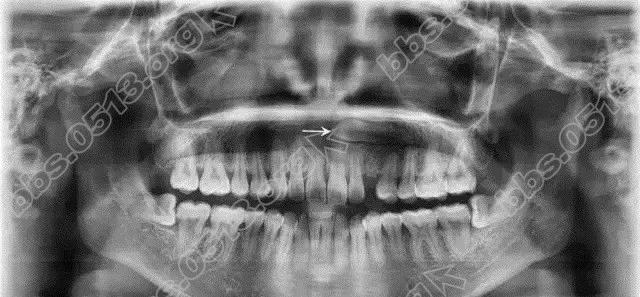

牙博士矫正真人案例

640.webp (2).jpg

640.webp (3).jpg

640.webp (4).jpg